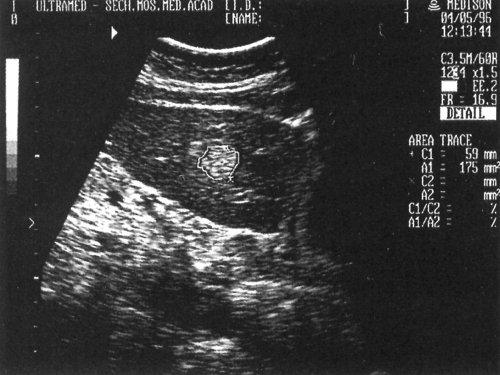

Рис. 9. Эхографическая картина одного из вариантов изображения капиллярной гемангиомы левой доли печени.